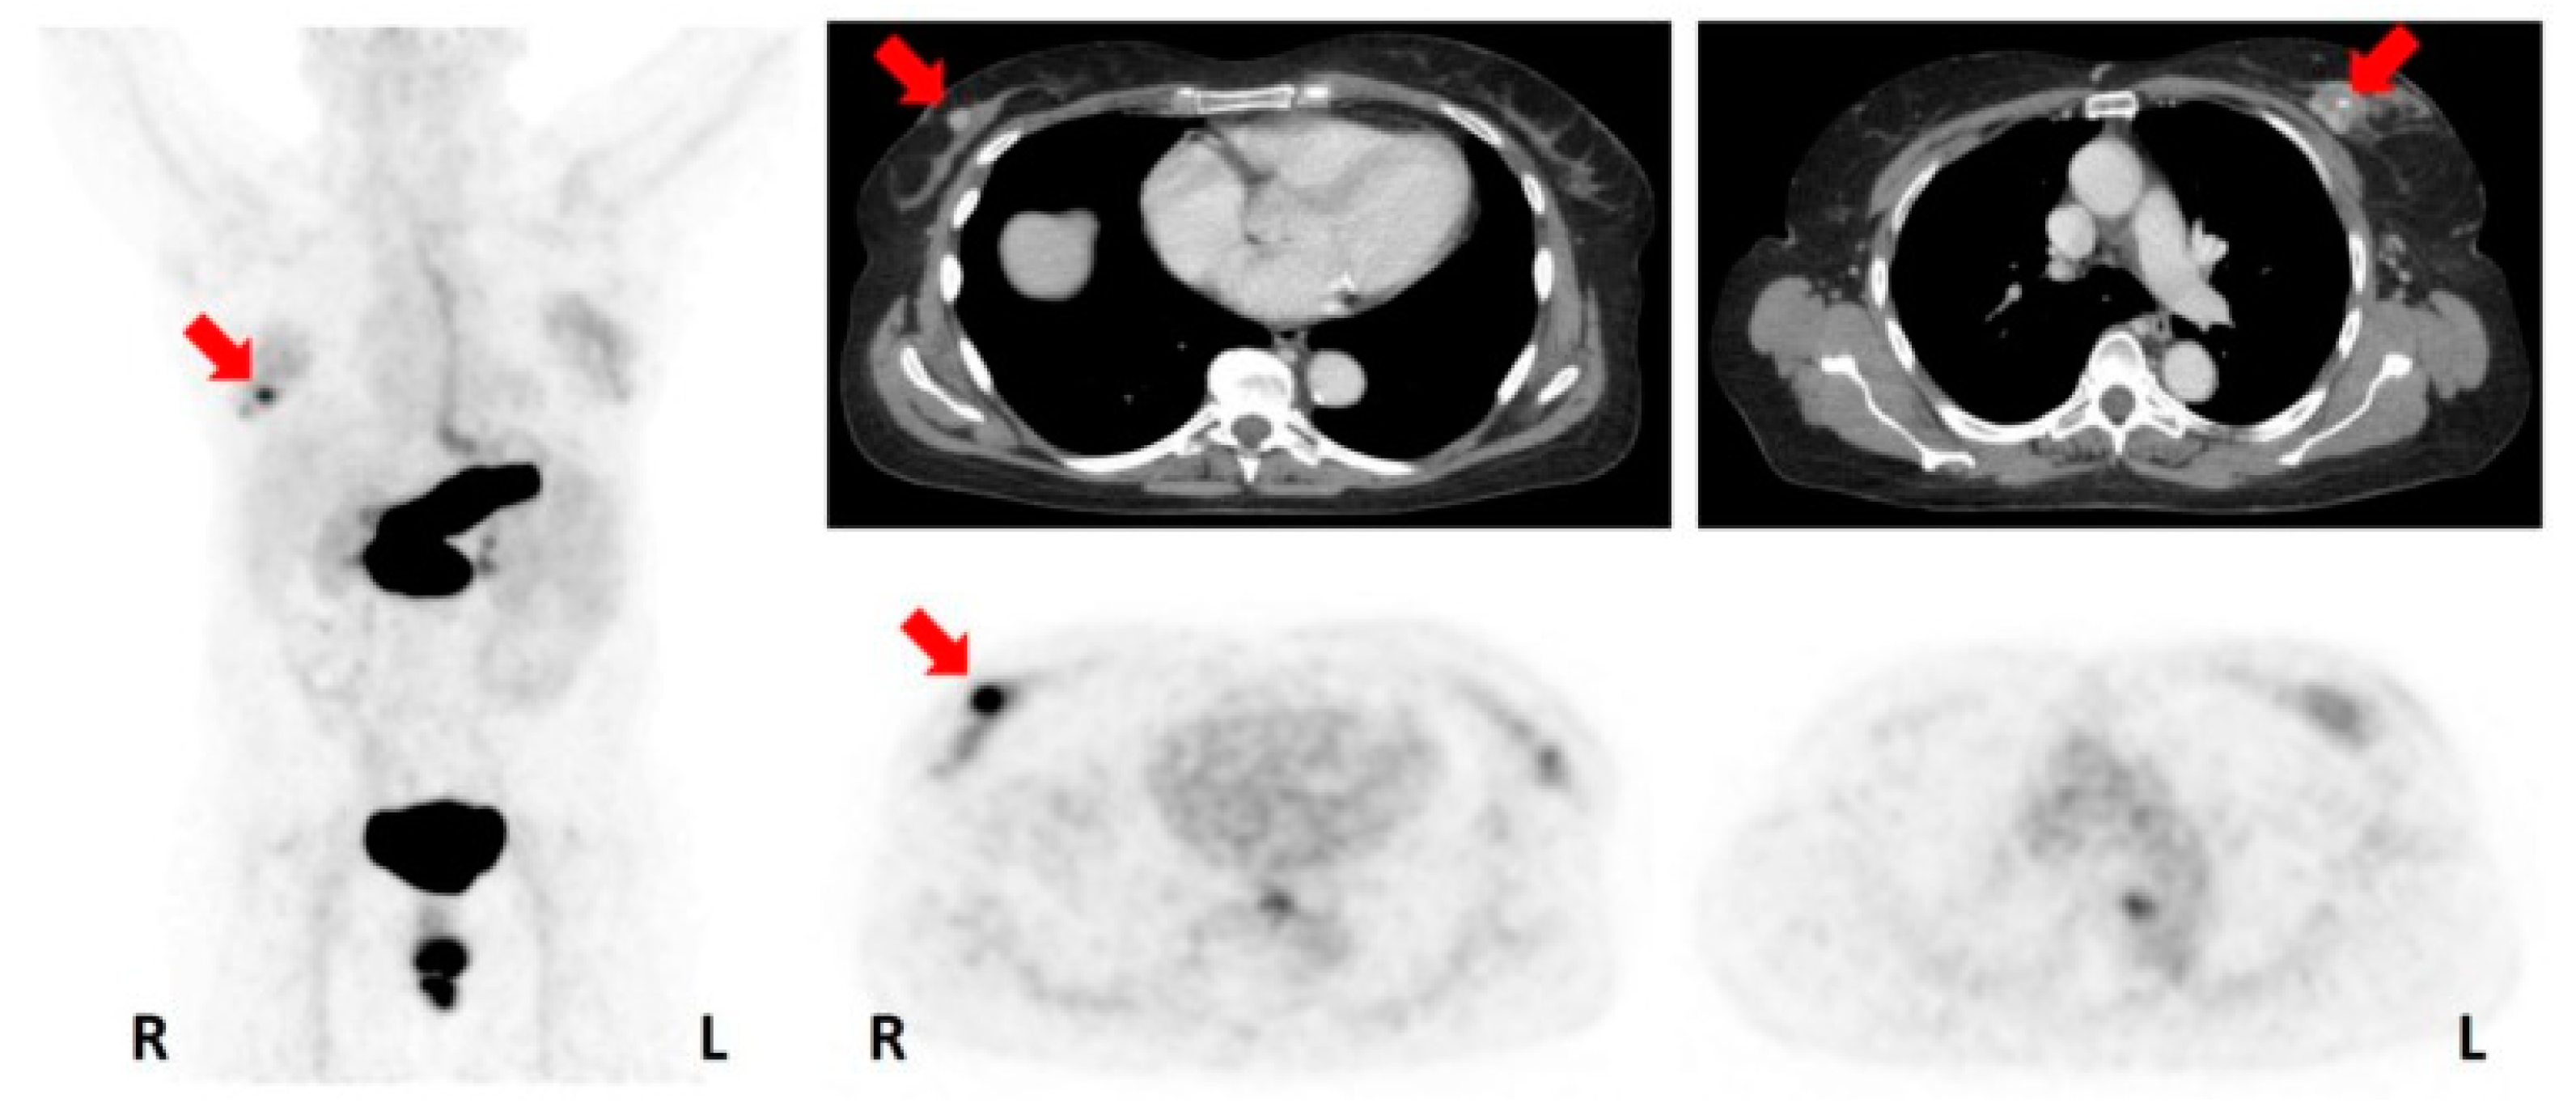

- Vag, T.; Steiger, K.; Rossmann, A.; Keller, U.; Noske, A.; Herhaus, P.; Ettl, J.; Niemeyer, M.; Wester, H.J.; Schwaiger, M. PET imaging of chemokine receptor CXCR4 in patients with primary and recurrent breast carcinoma. EJNMMI Res. 2018, 8, 90. [Google Scholar] [CrossRef] [PubMed]